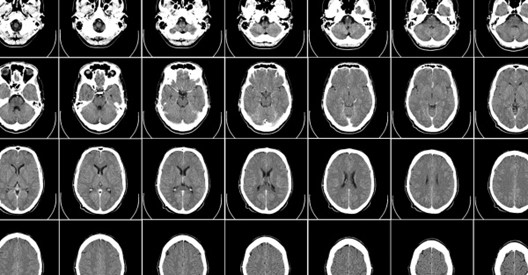

Cardoso是教师、CTO、企业家,也是 MONAI 开源联盟的创始成员以及医学影像AI领域的研究人员。作为上述最后一个角色,Cardoso和他的团队发现了利用AI创建高分辨率的人脑真实 3D 图像的方法。

这位伦敦国王学院的研究人员兼伦敦 AI 中心的CTO为医疗健康研究人员免费提供了10万张合成大脑图像。这是一个宝库,可以加速人类对痴呆症、衰老或各类脑部疾病的认知。

这种新型AI方法的重要特征是,它可以根据需要制作图像。女性大脑、男性大脑、老年人的大脑、年轻人的大脑、患有疾病或健康的等等,只需插入所需内容,系统就会进行创建。

虽然这些图像是模拟生成的,但非常实用,因为它们保留了关键生物特征,所以外观和运作方式与真实大脑高度相似。

不仅于此,团队还在探索这些模型如何在医学成像模式下(MRI、CAT 或 PET 扫描等)为人体任意部位生成 3D 图像。

合成图像将帮助研究人员了解疾病如何随时间推移而发展。与此同时,Cardoso的团队仍在探索如何将这项工作应用于大脑以外的身体部位,以及何种合成图像(MRI、CAT、PET)更实用。